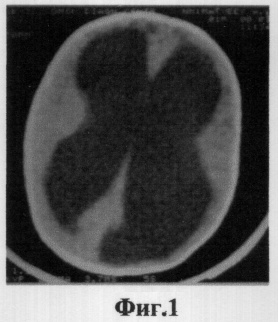

Фиг.1 Ребенку М. 6 месяцев выполнено вентрикулоперитонеальное шунтирование по поводу прогрессирующей внутренней гидроцефалии. До операции при КТ определена тяжелая степень гидроцефалии (ЛКИ = 51,5%).